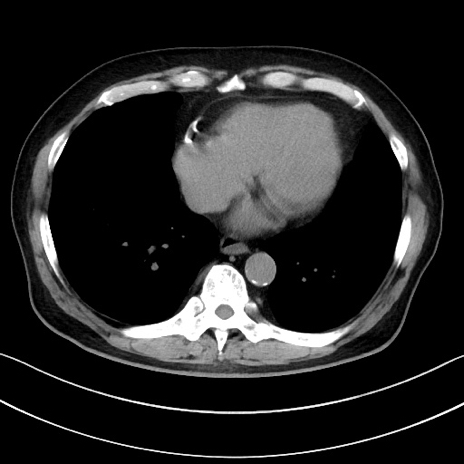

症例15(横断像)

【症例】70歳代男性

【主訴】腹痛

【現病歴】今朝から腹痛あり。全体的に痛い。特に左上の方。排ガスが今日はない。冷や汗が出る。

【既往歴】直腸癌術後

【身体所見】左側腹部〜上腹部に圧痛あり。腹膜刺激症状明らかなではない。軽度反跳痛。左下腹部に術後瘢痕あり。

【データ】WBC 7700、CRP 0.02